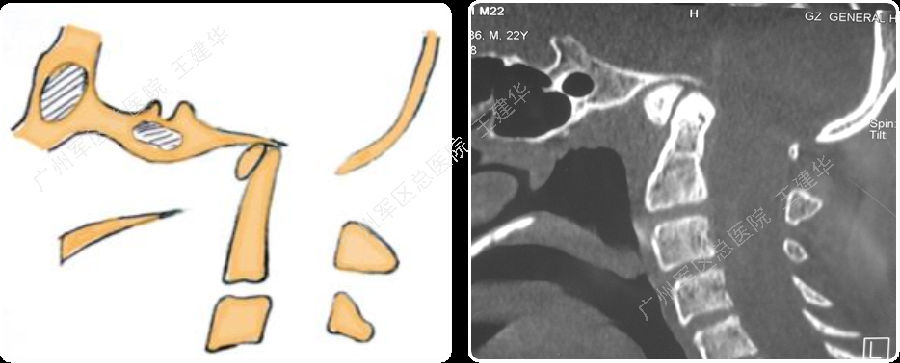

颈椎MR检查提示:颈椎上端结构陷入枕骨大孔,脑干受压变形

本例患者手术过程

手术复位过程

手术完成

手术前后对比

可以看到:

陷入枕骨大孔的寰椎和齿突已经下拉复位,枕颈排列恢复正常

脑干压迫解除,延髓脊髓角恢复正常

手术后6年复查:

颅颈椎序列恢复正常并骨性融合